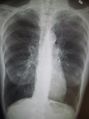

قد يفيد تصوير الصدر بالأشعة السينية والعد الدموي الشامل في استبعاد أسباب أخرى في وقت التشخيص.[52] والسمات المميزة للأشعة السينية هي التمدد الشديد للرئتين، وانبساط الحجاب الحاجز، وزيادة حيز الهواء خلف القص، والأمراض الجلدية، في حين أنها قد تساعد في استبعاد أمراض الرئة الأخرى مثل ذات الرئة ووذمة الرئة أو الاسترواح الصدري.[53] يمكن لصورة الصدر عالية الوضوح باستخدام التصوير المقطعي المحوسب بالأشعة السينية أن تبين توزيع النفاخ الرئوي في جميع أنحاء الرئتين ويمكن أيضاً أن تكون مفيدة في استبعاد أمراض الرئة الأخرى.[11] إذا لم يكن مخططاً لإجراء عملية جراحية، فهذا نادراً ما يؤثر على العلاج.[11] ويتم استخدام غازات الدم الشرياني لتحديد مدى الحاجة إلى الأكسجين؛ ويوصى به لمن يُتوقع أن يكون حجم الزفير القسري لديهم1 أقل من 35%، والذين لديهم تشبع أكسجين محيطي أقل من 92% والذين تظهر لديهم أعراض قصور القلب الاحتقاني.[10] في مناطق العالم التي يشيع فيها نقص مضاد التريبسين ألفا-1، يجب أن يوضع في الاعتبار اختبار الأشخاص المصابين بمرض الانسداد الرئوي المزمن (خاصة من هم دون سن 45 ولديهم نفاخ رئوي يؤثر على الأجزاء السفلية من الرئتين).[10]